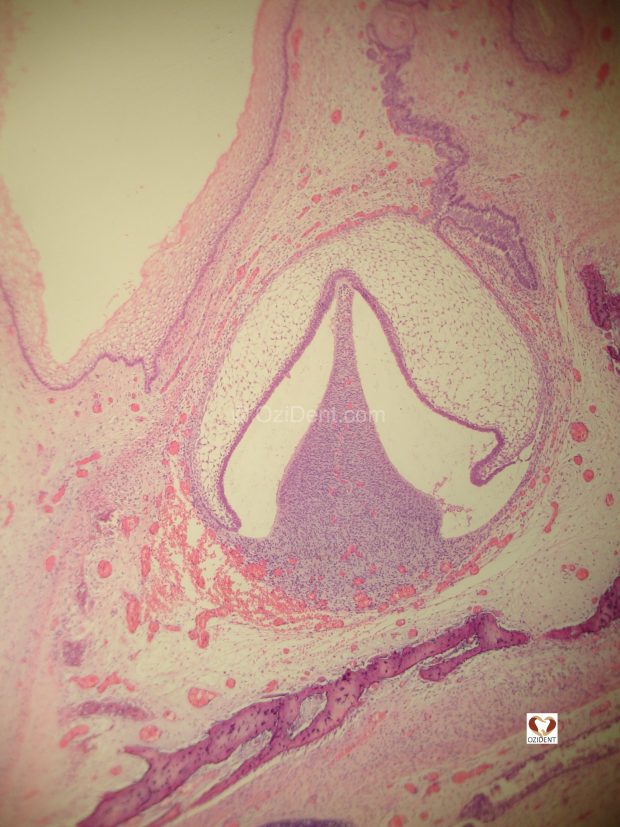

From www.ozident.com

Late Bell Stage (21) OziDent What Is A Late Bell This system is widely used aboard ships to. The late bell stage (appositional stage) of tooth development is associated with the formation of the dental hard tissues. The bell itself is usually made of. Study with quizlet and memorize flashcards containing terms like what is significant about the school late bell?, marcato, what are the notes. Explore the different bell. What Is A Late Bell.

From www.researchgate.net

H and E staining of a deciduous tooth germ at the ''late bell'' stage What Is A Late Bell 9 rows ship's bells explained. The bell itself is usually made of. A ship's bell is a bell on a ship that is used for the indication of time as well as other traditional functions. After the bell stage is the late bell stage, or the crown stage. Study with quizlet and memorize flashcards containing terms like what is significant. What Is A Late Bell.